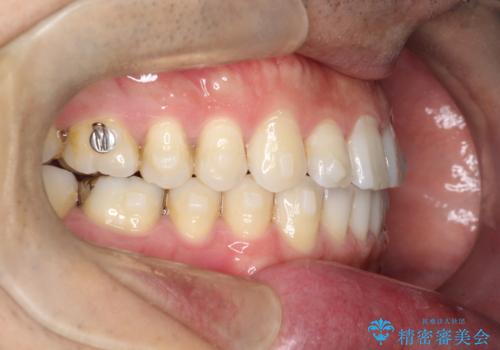

【インビザライン】前歯の隙間を閉じたい

- 前歯の隙間を主訴に来院されました。

マウスピース矯正にて、隙間を綺麗に閉じることができ満足していただきました。

前歯の隙間を閉じる際は、前歯部の突き上げが懸念されるため、適切な治療計画が必要となります。